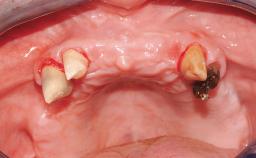

Immediate Loading of Four Implants in the Mandible and Six Implants in the Maxilla and Final Restoration with a Full-Arch Metal Framework FDP and a Full-Arch CAD/CAM Zirconia Framework FDP

A 65-year-old female patient with a failing residual maxillary dentition and a complete mandibular removable denture was referred for consultation and treatment. The patient’s chief complaint was that her upper residual teeth were mobile and she was unable to chew. The patient also asked us to improve the esthetic appearance of her smile. The patient’s desire was a stable and comfortable dentition in both jaws, and she specifically asked for a fixed rehabilitation. The patient reported a history of recurrent caries, endodontic complications, and periodontal disease as main reasons for previous teeth extractions. The anamnesis was negative for bruxism and TMJ disorders. The patient had no systemic diseases, was not on any medication,and did not smoke. The extraoral examination revealed a medium lip line, a wide diastema between the two central incisors (which, according to the patient, had appeared recently), and a partial collapse of the perioral soft tissues, probably due to loss of the correct vertical dimensions.